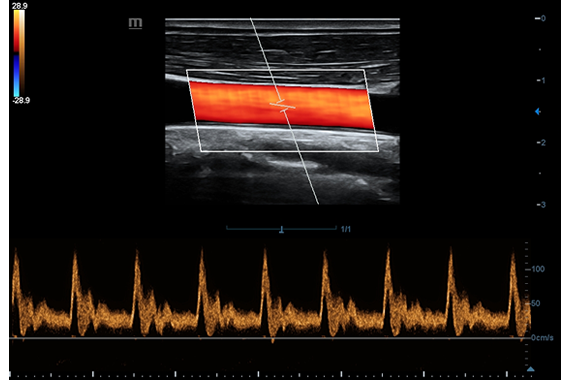

X-Insight es una soluci├│n inteligente para un mejor diagn├│stico.

El DC-60 Exp con X-Insight es un colaborador vers├Ītil que proporciona una soluci├│n integral para ayudarlo a administrar todos los aspectos de la pr├Īctica cl├Łnica diaria con facilidad y seguridad.

Basado en los profundos conocimientos de las necesidades del cliente, el DC-60 Exp con X-Insight est├Ī dise?ado para ofrecer una alta eficiencia con im├Īgenes de precisi├│n, que se potencia con eXpress Clarity, eXceptional Intelligence y eXceeding Experience.